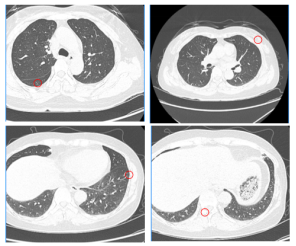

腹部增强MRI:乙状结肠及降结肠交界处癌,浸润浆膜层,灶周散在小淋巴结;Ⅴ-Ⅵ段交界处占位:考虑转移瘤(大小3.0*2.5cm)。

image.png 图1 腹部增强MRI